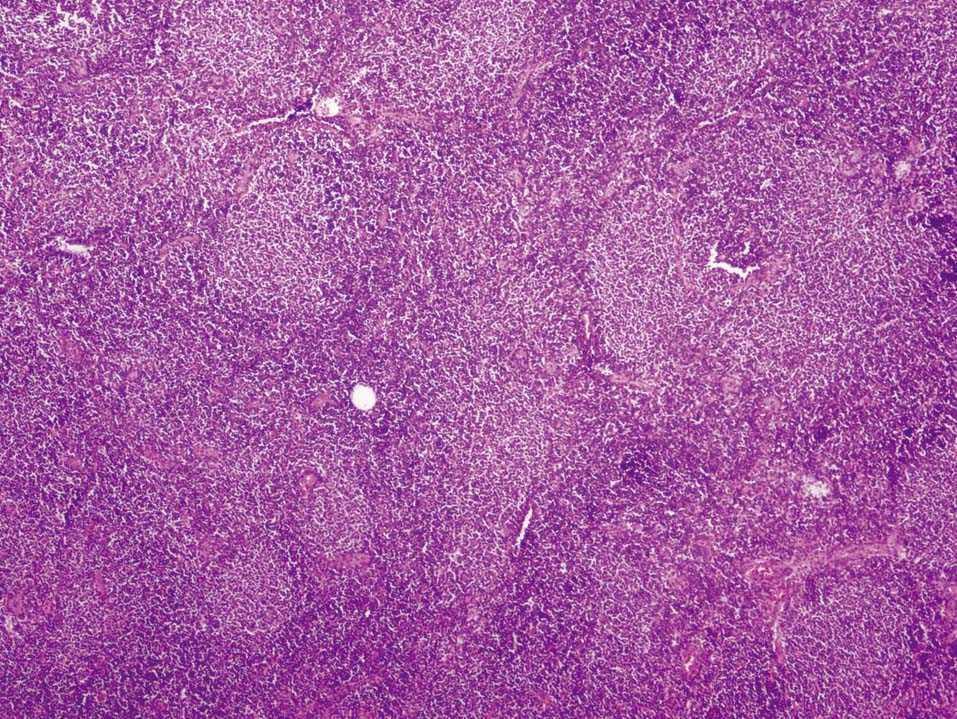

En octubre de 2005 presentó una tumoración en el cuadrante superoexterno (CSE)-cola de la mama izquierda, por lo que se la remitió a nuestro servicio. La paciente tenía en ese momento 59 años. A la exploración se objetivó un nódulo móvil, bien definido y profundo en el CSE de la mama izquierda. El estudio mediante PAAF informó de ganglio linfático con presencia de celularidad polimorfa con predominio de linfocitos de pequeño tamaño. El CA15.3 fue de 16-50 U (rango de normalidad < 38). Se realizó una biopsia diferida y se obtuvieron 2 fragmentos de tejido fibroadiposo de 6 × 5,3 × 5,2 cm y de 6,5 × 5,5 × 2,5 cm de máximas dimensiones. Tras cortes seriados, en el segundo fragmento se observó un nódulo bien delimitado de superficie blanquecina y aspecto homogéneo de 22 × 17 mm. Microscópicamente, correspondía a un ganglio linfático con borramiento de su arquitectura debido a la presencia de una proliferación neoplásica de estirpe linfoide que adoptaba un patrón de crecimiento predominantemente nodular. El tumor estaba compuesto por linfocitos de pequeño tamaño con escaso citoplasma, núcleo hipercromático, hendido y de contorno irregular, y se observó menos de un 5% de células grandes o centroblastos (figs. 1 y 2). Con técnicas de inmunohistoquímica, las células tumorales expresaron CD20 (fig. 3) y CD10 (fig. 4), mientras que fueron negativas para CD3, bcl-2 y CD23. El índice de proliferación celular (Ki67) fue del 10%. El diagnóstico anatomopatológico fue de linfoma no Hodgkin B del centro folicular de grado I (90% nodular).

Figura 1.Linfoma no Hodgkin B del centro folicular: proliferación neoplásica constituida por linfocitos de pequeño y mediano tamaño, con un patrón de crecimiento predominantemente nodular (hematoxilina-eosina, ×20).